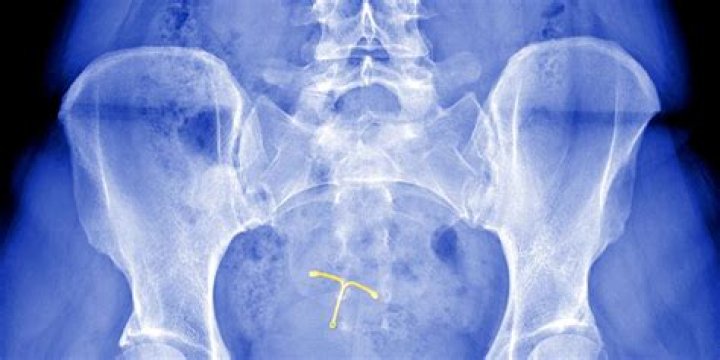

Why is the Mirena IUD being recalled?

Mirena lawsuits accuse Bayer Pharmaceuticals of hiding side effects and making a defective intrauterine uterine device (IUD). Women blame the birth control device for organ perforation, dislodging from the uterus and causing pressure buildup in the skull.